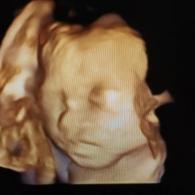

試管嬰兒技術(shù)作為輔助生殖技術(shù)的一種,已經(jīng)幫助無數(shù)家庭實(shí)現(xiàn)了擁有孩子的愿望。試管嬰兒技術(shù)分為一代、二代和三代,它們在技術(shù)原理、適用人群、成功率等方面存在差異。本文...